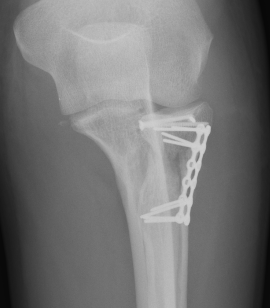

ORIF with plates

Lateral approach

- identify safe zone (90 degrees between radial styloid) and Lister's tubercle)

- lag articular surface first if required

- pre-contoured low profile plates

- distal limit is bicipital tuberosity

- check ROM intra-operatively

- plates often bulky and may limit ROM

- close annular ligament